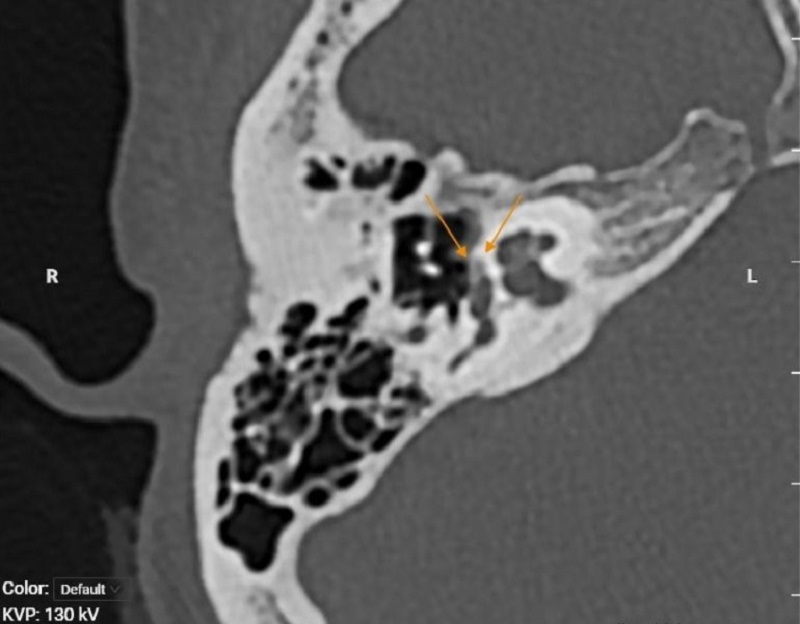

Để xác định nguyên nhân gây triệu chứng bất thường, bác sĩ chỉ định chị G. thực hiện nội soi tai mũi họng và chụp CT xương thái dương. Kết quả chụp cho thấy hình ảnh xương bàn đạp dính vào cửa sổ bầu dục. Không thấy trật khớp đe - đạp. Phía trước cửa sổ bầu dục có ổ nhuyễn xương là dấu hiệu điển hình của bệnh xốp xơ tai (Otosclerosis)

Hình ảnh chụp CT xương thái xương của chị G. ghi nhận hình ảnh xương bàn đạp dính vào cửa sổ bầu dục. Không thấy trật khớp đe-đạp. Phía trước cửa sổ bầu dục có ổ nhuyễn xương nhỏ, đường kính 1.2mm, ranh giới rõ bờ đều.

ThS.BS Trần Xuân Tiến - Trung tâm Chẩn đoán hình ảnh MEDLATEC chia sẻ: Trong các phương pháp chẩn đoán hình ảnh hiện nay, chụp cắt lớp vi tính (CT-scanner) xương thái dương được xem là phương pháp đầu tay trong đánh giá và chẩn đoán các bệnh lý liên quan đến tai giữa và tai trong. Kỹ thuật này cho phép bác sĩ quan sát chi tiết cấu trúc xương bàn đạp, cửa sổ bầu dục và mê nhĩ, từ đó xác định chính xác vị trí và mức độ tổn thương.

Trên phim CT có thể nhận thấy vùng giảm tỷ trọng (hypodense) quanh cửa sổ bầu dục, đặc biệt ở vị trí phía trước cửa sổ bầu dục - dấu hiệu điển hình của fenestral otosclerosis.

Hình ảnh cho thấy vùng xương đặc, dày hơn bình thường, có thể gây hẹp cửa sổ bầu dục hoặc cố định đế bàn đạp, ảnh hưởng đến dẫn truyền âm thanh.